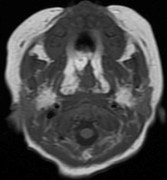

1899. У ребенка при выполнении МРТ в просвете глотки, на уровне от хоан до надгортанника, определяется опухолевое образование неоднородной структуры интенсивно, неоднородно накапливающее контрастный препарат, без явного распространения за пределы стенки глотки, что соответствует